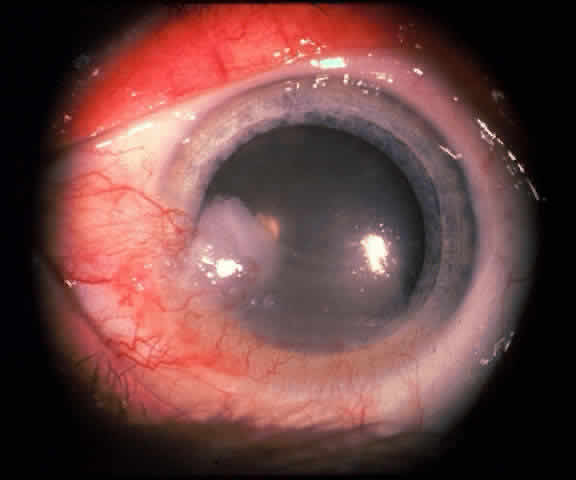

The epithelial dysplastic lesions—conjunctival intraepithelial neoplasia and squamous cell carcinoma—almost always begin at the limbus, most commonly in the interpalpebral zone.57,58 The initial appearance is a gelatinous, gray lesion with some thickening (Fig. 3). There may be increased vascularization. The epithelial changes may extend onto the cornea, causing a hazy, gray appearance. Tumor vascularity lags behind the lead margin of the epithelial change. As the lesions progress from dysplastic to carcinomatous, they become thicker, more vascularized and may show keratinization, giving a leukoplakic appearance (Fig. 4). Lesions confined to the epithelium move freely over the sclera, whereas invasive lesions are fixed to underlying tissue. Occasionally squamous cell carcinomas appear identical to classic papillomas.

Fig. 8. Conjunctival intraepithelial neoplasia. Gray, gelatinous mass is centered at limbus and has prominent vessels. A veil of intraepithelial disease extends laterally across the inferior third of the cornea.

Fig. 9. Squamous cell carcinoma of conjunctiva.